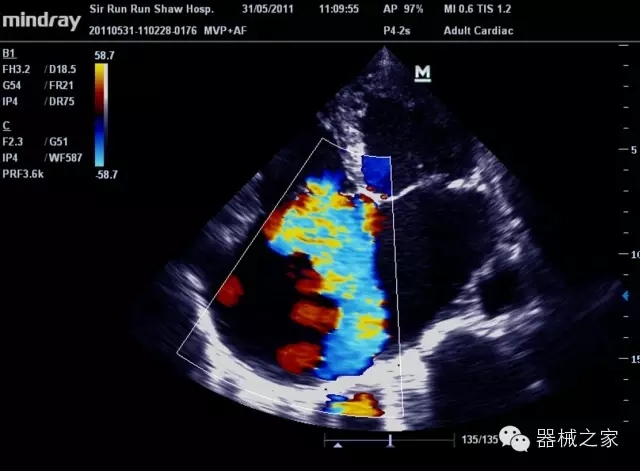

經(jīng)典產(chǎn)品:M7(星鉆)

臨床圖片賞析

產(chǎn)品特點(diǎn)

·裝載有采用Multi-Core多核處理的非嵌入式平臺,成像效率大大提高,并且能夠給用戶帶來高速、多任務(wù)并行信號處理體驗(yàn);

·優(yōu)秀的圖像效果、強(qiáng)大的功能體驗(yàn)、豐富的探頭選擇、合理的便攜式設(shè)計(jì),全中文顯示及病人管理界面,使得M7在任何場合、任何時(shí)候都能快速響應(yīng)更好的心血管、腹部、婦產(chǎn)、小器官等常規(guī)超聲檢查以及肌骨、神經(jīng)、顱腦、術(shù)中等新興領(lǐng)域的使用需求;

8倍波束并行處理系統(tǒng)

·在便攜式緊湊平臺上采用更多倍波束并行接收信號處理模式,無論二維還是彩色血流圖像狀態(tài)下,擁有更靈敏的回波頻移捕獲能力,大大提高時(shí)間分辨率,尤其使得心血管表現(xiàn)更為突出;

PSHI?寬帶頻移諧波技術(shù)

·在普通組織諧波的基礎(chǔ)上,通過精確控制的波束形成器,發(fā)射兩組具有相位偏差反向的信號,并采用并行信號處理,數(shù)字化合成并采樣回波信號,在高靈敏度的濾波器的處理過程中獲取更純凈的諧波信號,使圖像具有更加出眾的細(xì)節(jié)分辨率;

iClear®+iBeam?

·智能化按線復(fù)合多角度獲取聲束的原始信號,配合智能化的斑點(diǎn)噪聲識別及控制處理技術(shù),整體提高組織結(jié)構(gòu)細(xì)節(jié)分辨率,任何時(shí)候都能快速響應(yīng),更好的滿足心血管的使用需求;

支持全新3T工藝探頭群

·包括探頭材料、結(jié)構(gòu)設(shè)計(jì)、加工工藝三方面的革新技術(shù)給圖像帶來品質(zhì)的飛躍;

CFDA注冊證編號

·粵食藥監(jiān)械(準(zhǔn))字20132230475